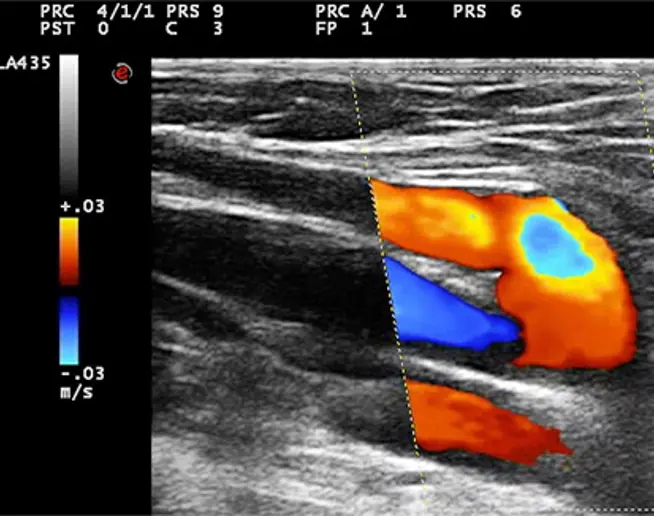

在局部麻醉下进行的微创手术,并配合术前B超定位标记。